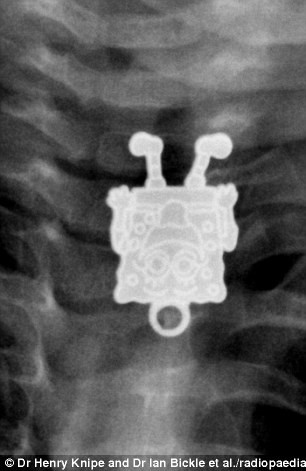

Un baietel din Arabia Saudita a inghitit o jucarie SpongeBob Squarepants. Medicii au fost uimiti sa vada jucaria zambindu-le din radiografie, scrie The Mirror.

Ei au crezut initial ca cel mic a inghitit o agrava, insa la o privire mai atenta au observat ca era SpongeBob.

„Din lateral parea un obiect lunguiet, ca o agrava, dar la vedere frontala a aparut altceva. Am fost uimit de detalii. Ii poti vedea pistruii, pantofii si degetele”, a afirmat medicul Ghofran Ageely, de la Spitalul din Jeddah.